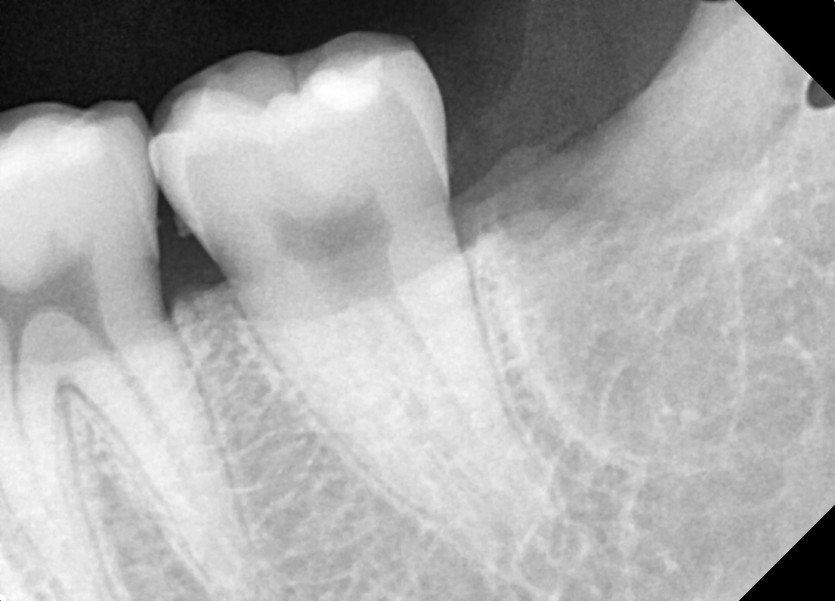

#28,38 사랑니 발치

구강 외과 전문의가 당일 발치했습니다.